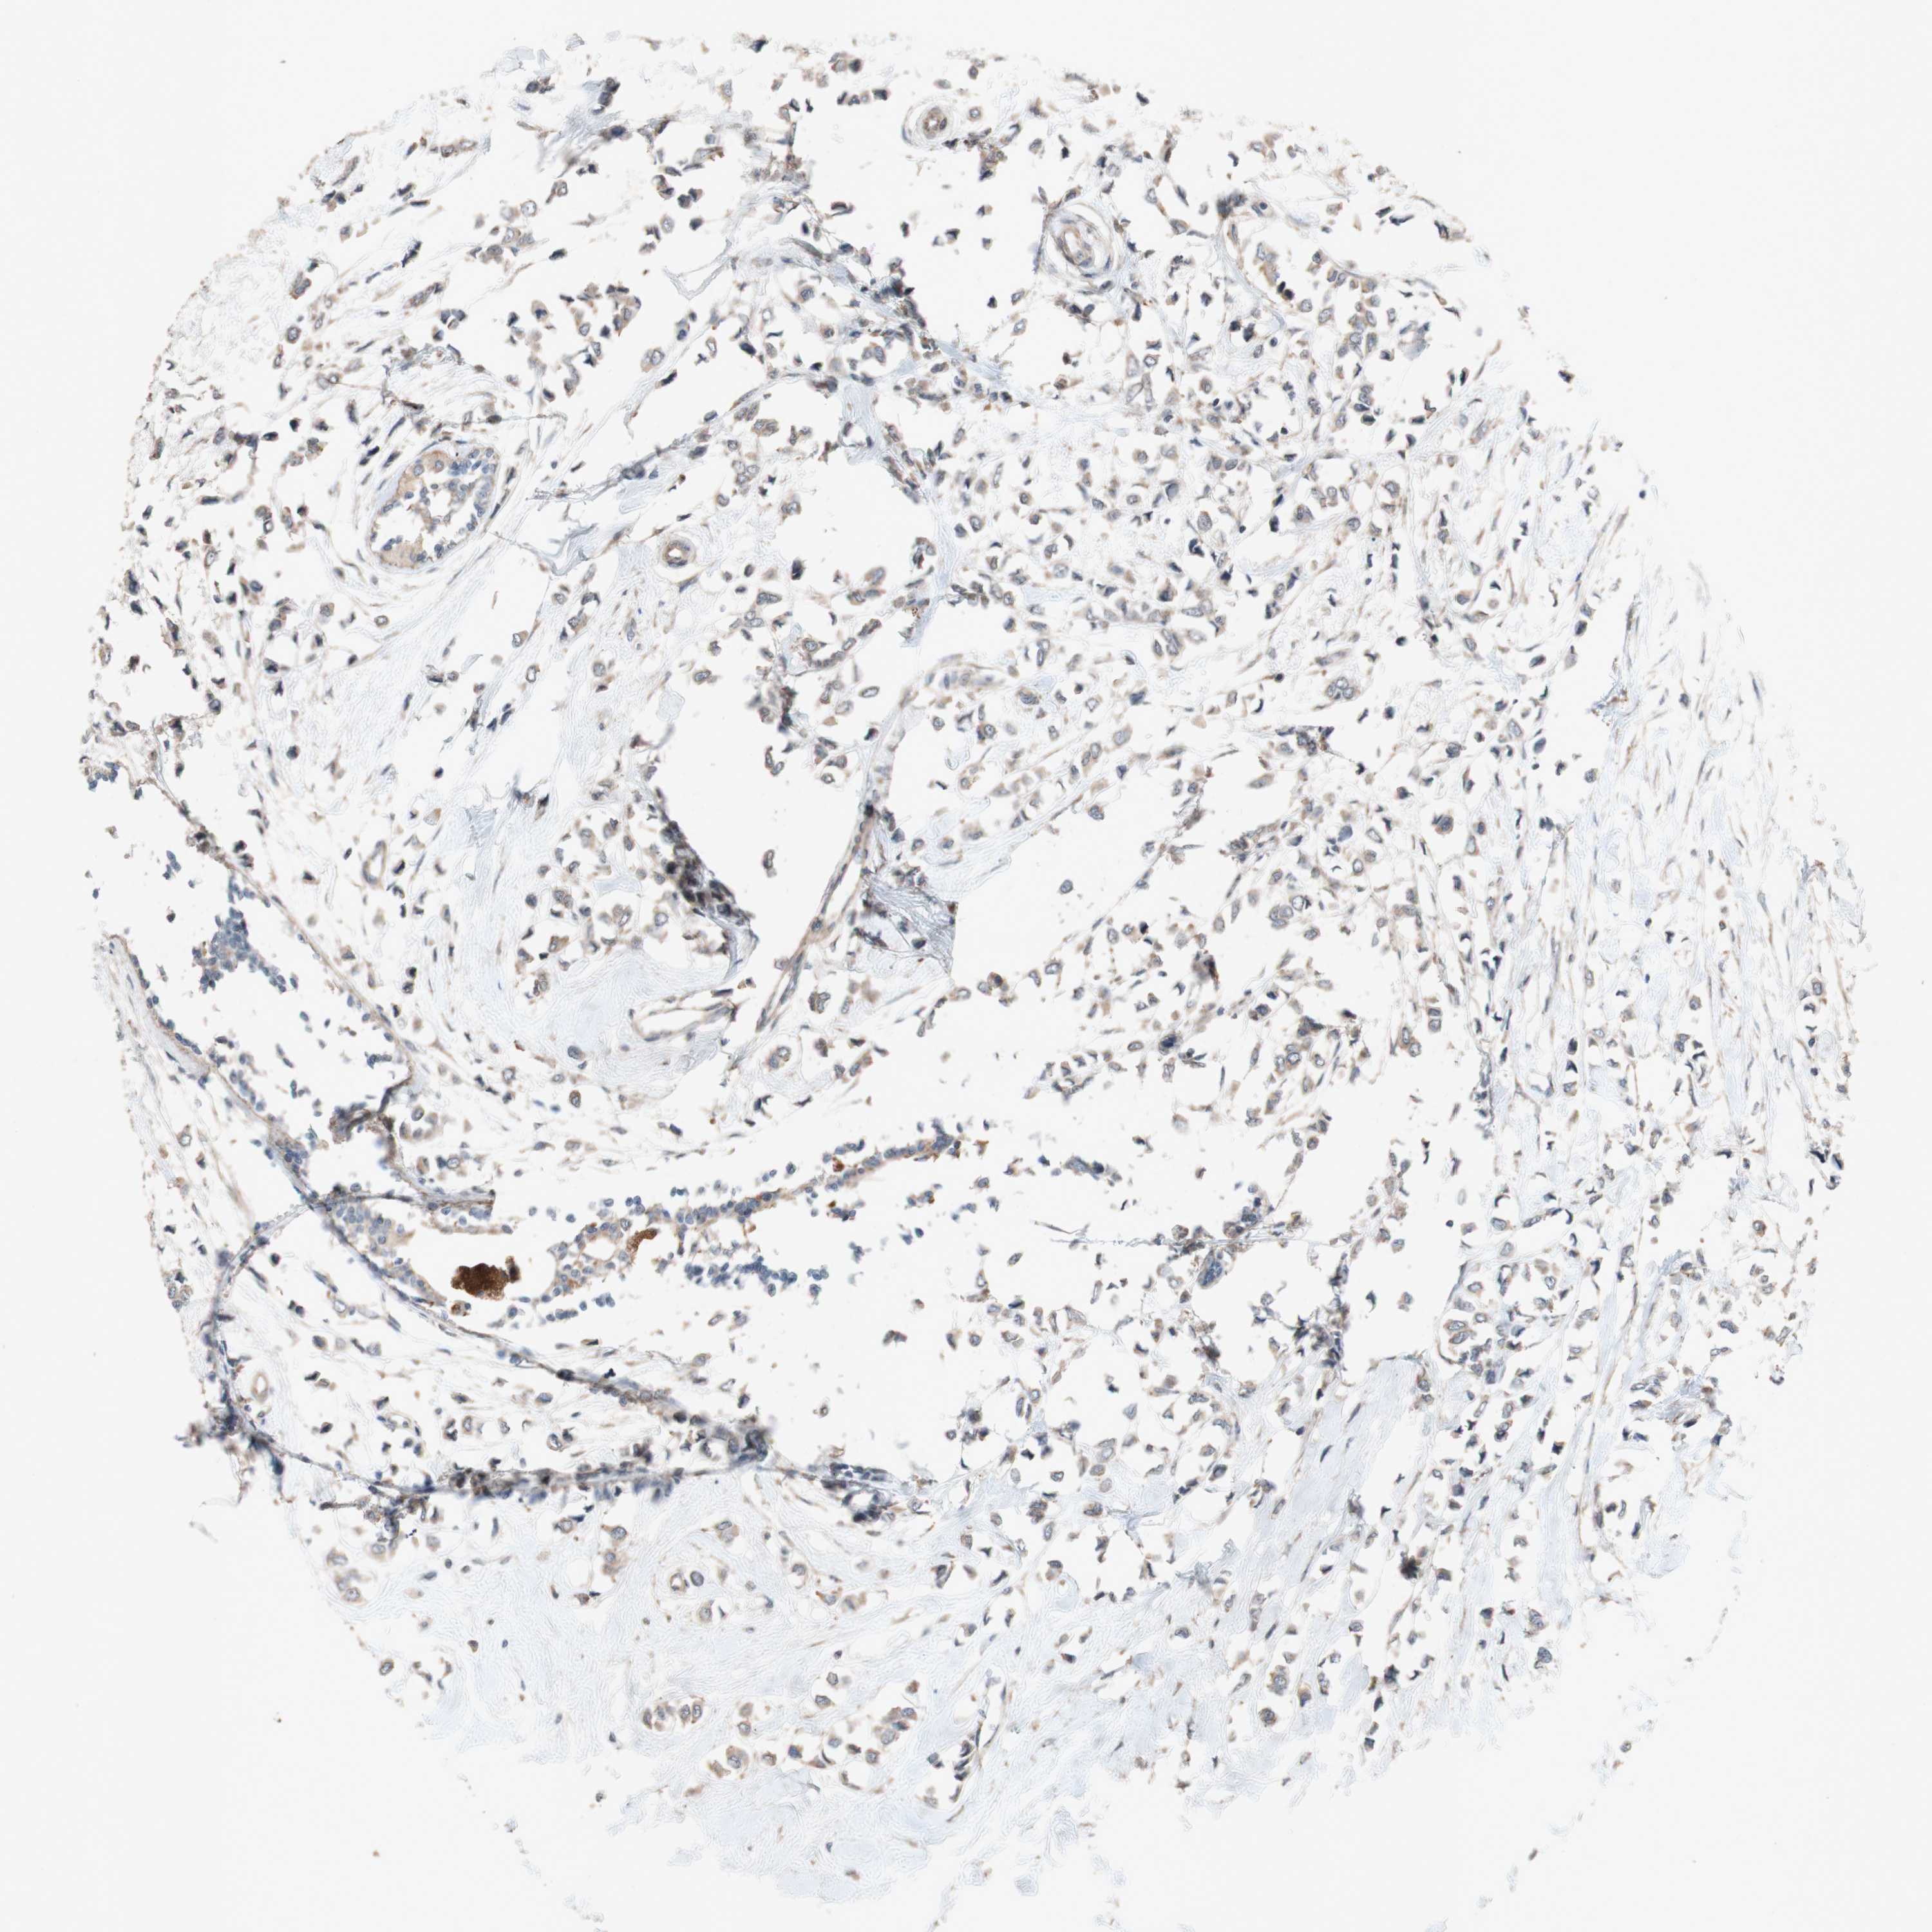

BRCA TCGA BRCA VALIDATION PROTEIN EXPRESSION